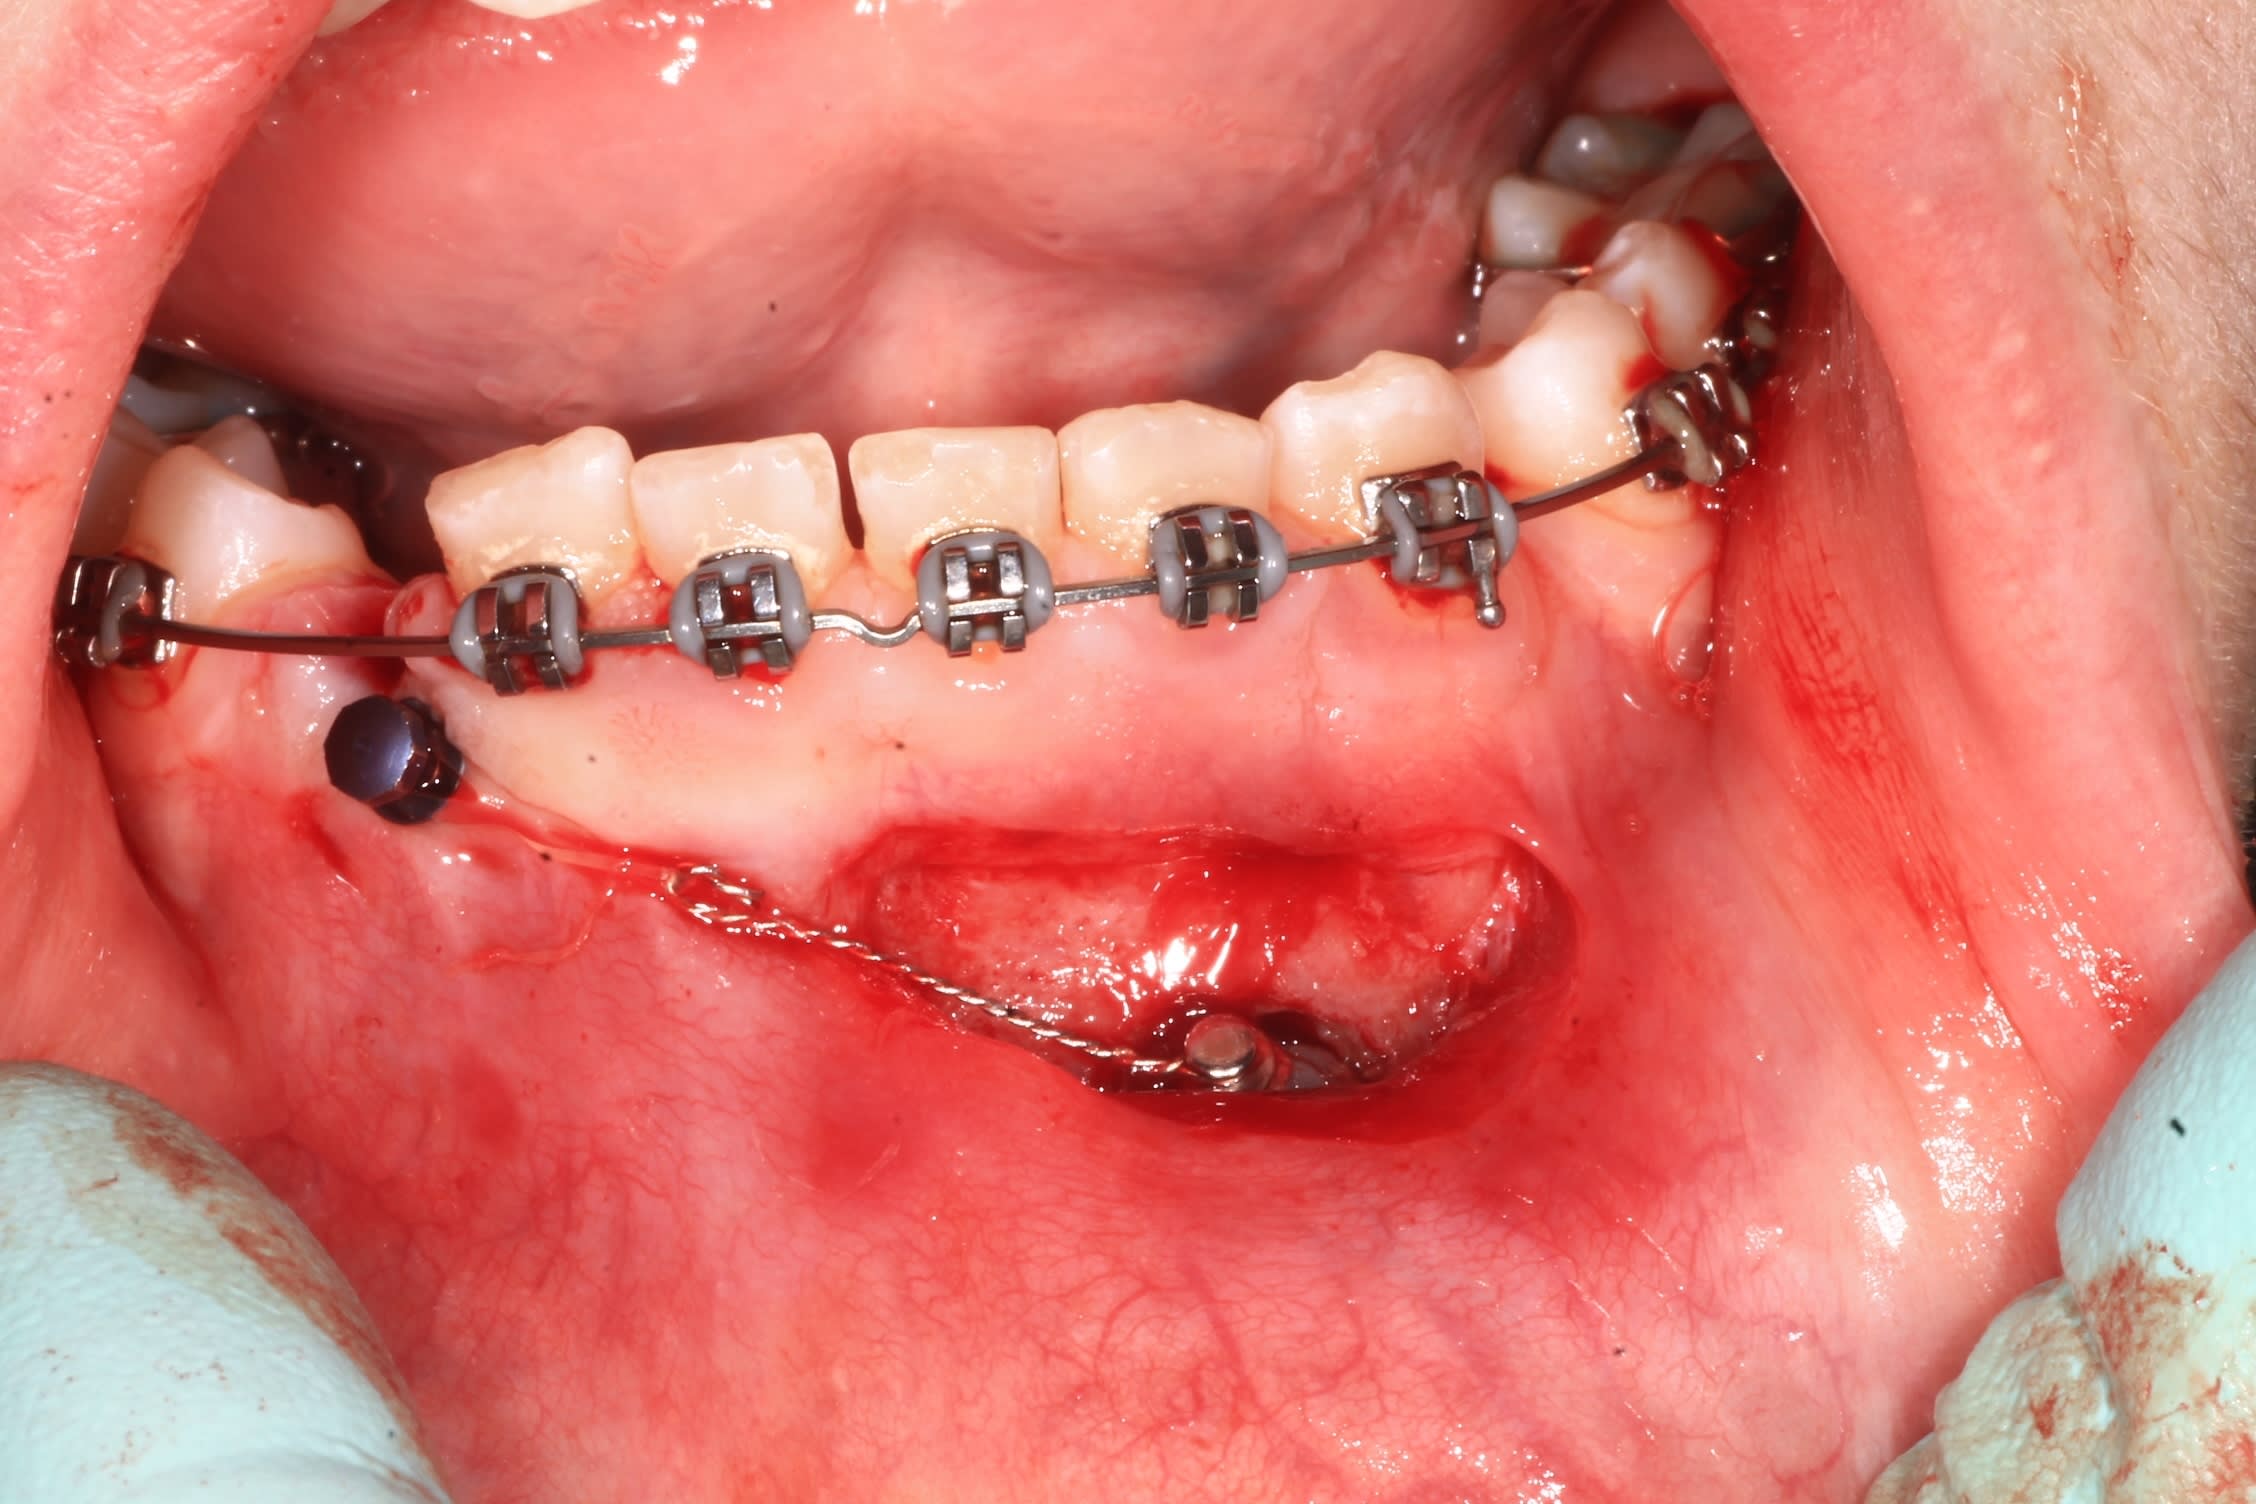

Voici un exemple de traction de canine incluse inférieure. Il faut absolument laisser les incisives inférieures totalement libres pour qu'elles puissent un peu se déplacer spontanément si nécessaire.

La supériorité du CT8 sur n'importe quel autre ancrage pour tracter les canines incluses tient en particulier à sa longueur qui permet des forces légères (25g), avec une grande amplitude de mouvement en direction contrôlée. Prévois bien un retour du fil suffisamment long après sa pliure au niveau de la ligature pour avoir de la marge. Tu pourras alors le déplier et le replier différemment en cours de traitement si tu veux, un moment donné, modifier la direction de la force. On a en effet toujours tendance à le couper trop court.

Amuse-toi bien et tiens nous au courant.

Bon, par contre, il va falloir que reintervenne un peu.

l'arcade est baguée, et j'ai mis une minivis, qui , comme je le pensais, provoque l'enfouissement de la chaînette dans la gencive :(

Mon patient sort du cab a l'instant, avec un CT8 tout neuf.

La traction avec la chainette sur minivis avait deja initié le travail.

je mettrais les pano a mesure de l'avancement du traitement.

C'est assurément un beau fil et une belle boucle, mais es-tu sûr que tes vis vont tenir ? Elles me paraissent bien hautes par rapport à la ligne oblique externe où on les place habituellement.